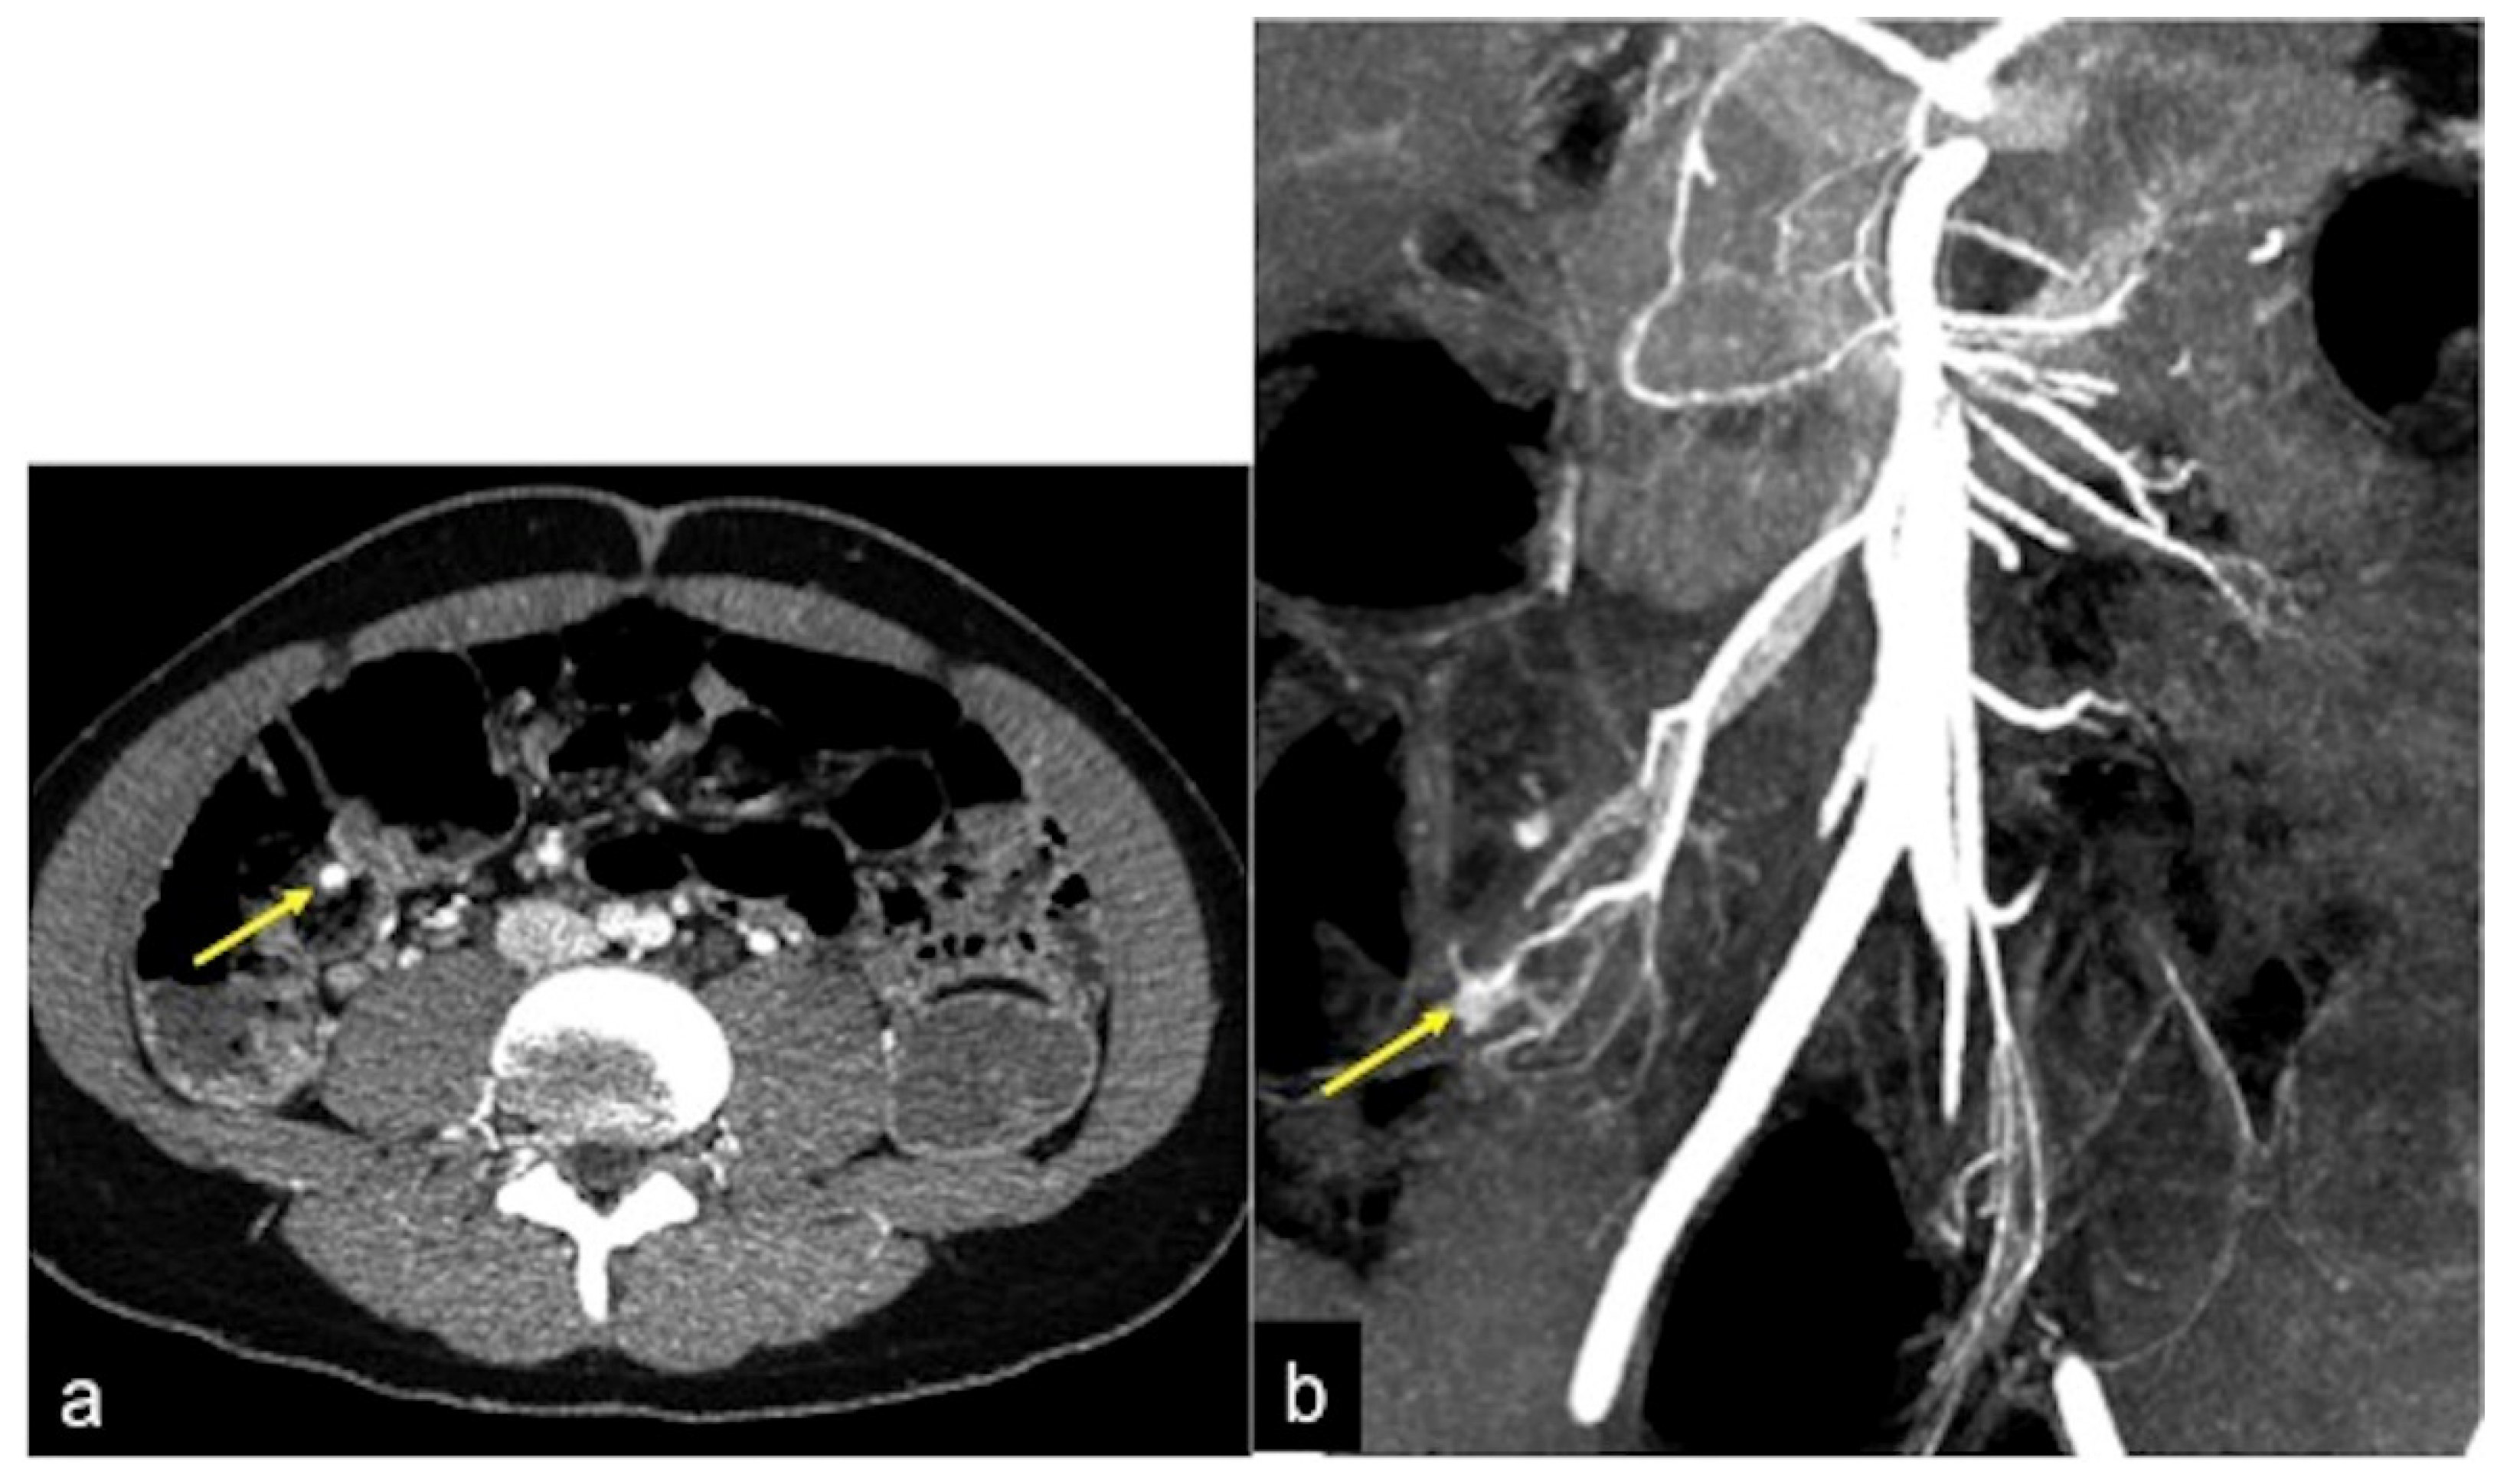

| Dieulafoy Lesion (Figure 27) | Melaena, haematemesis, haematochezia, or a combination of more than one of these signs, depending on the location of the lesion. | Abnormally enlarged submucosal vessel, which may appear tortuous, linear or as a non-specific “blush” of contrast medium at the mucosal/submucosal level. |